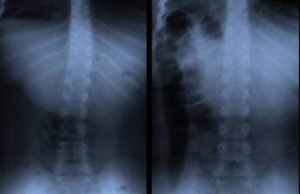

Deformiteti kičme kod dece – šta je skolioza i kifoza, njihova...

Razdoblje intenzivnog rasta i razvoja je najkritičnije kada su u pitanju kičmeni deformiteti kod dece. Kriva kičma kod dece je direktna posledica svakodnevnih životnih...